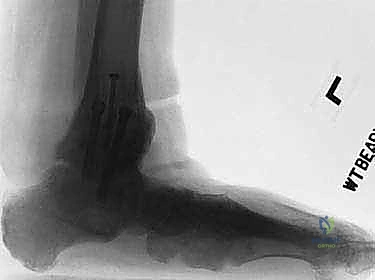

عملية تثبيت مفصل الكاحل والقدم الخلفية، والمعروفة طبياً بـ (Tibiotalocalcaneal Arthrodesis)، هي إجراء جراحي معقد يهدف إلى دمج (لحام) ثلاثة عظام رئيسية معاً لتكوين كتلة عظمية واحدة صلبة وغير متحركة. هذه العظام هي: عظمة الساق الكبرى (Tibia)، وعظمة الكاحل (Talus)، وعظمة الكعب (Calcaneus).

يتم هذا الدمج باستخدام مسمار نخاعي (Intramedullary Nail) طويل وقوي يُدخل من أسفل الكعب ليخترق العظام الثلاثة، ويتم تثبيته ببراغي قفلية لضمان أقصى درجات الثبات. الهدف من إلغاء الحركة في هذه المفاصل التالفة هو القضاء التام على الاحتكاك العظمي الذي يسبب الألم المبرح، مما يوفر للمريض قاعدة ثابتة وقوية للمشي.

يعتمد الدكتور هطيف على الأشعة السينية (X-rays) والأشعة المقطعية (CT Scans) ثلاثية الأبعاد لبناء خريطة دقيقة للتشوهات العظمية وتحديد حجم ومسار المسمار النخاعي المناسب لكل مريض بدقة متناهية. يتم مناقشة كل هذه التفاصيل بشفافية تامة مع المريض.

إذا كان هناك أي اعوجاج أو تشوه في القدم، يقوم الجراح بتعديل وضعية العظام (الساق، الكاحل، الكعب) لتكوين زاوية مثالية للمشي (عادة 90 درجة مع الساق).